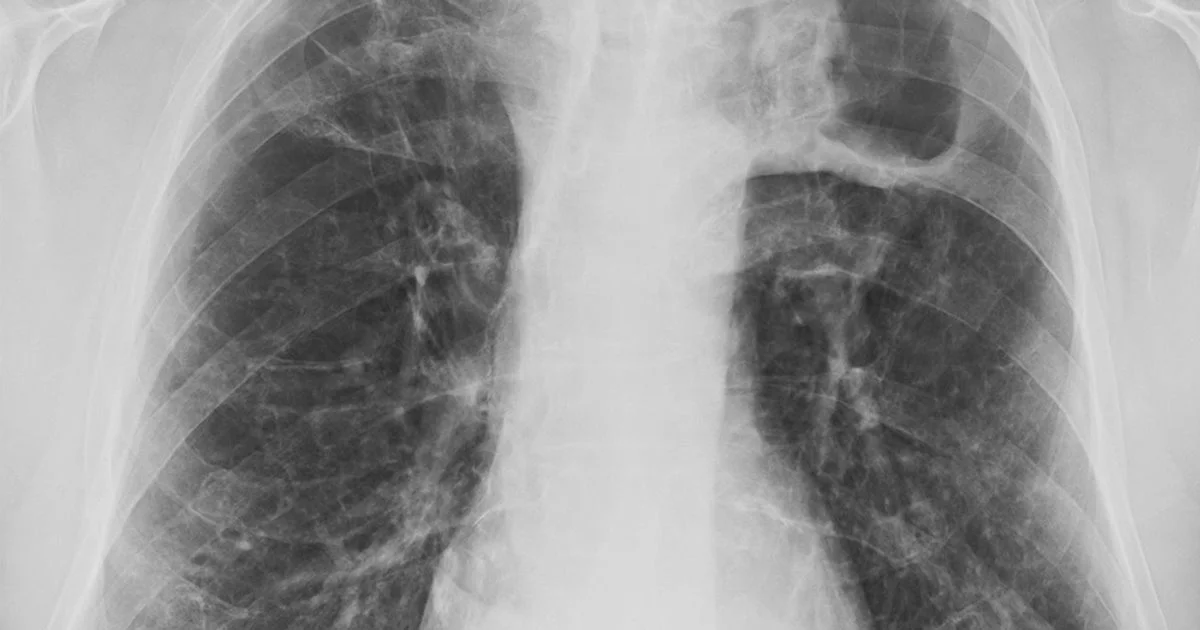

Concurrently, reports highlight ongoing concerns about tuberculosis (TB), a bacterial infection that primarily affects the lungs but can spread to other parts of the body. TB is described as a "Victorian-era illness," with experts warning of a "worrying surge" in some cases that are resistant to antibiotics. Data indicates that individuals born outside the UK account for a significant proportion of TB cases. While England is considered a low-incidence country for TB, rates remain elevated in urban areas like London.

Tuberculosis is a bacterial infection spread through the air, primarily affecting the lungs. Symptoms commonly include a persistent cough (lasting over three weeks), potentially with blood-tinged mucus, fatigue, fever, night sweats, loss of appetite, and weight loss.

TB can also manifest in other body parts, leading to symptoms such as body aches, swollen glands, joint pain, and changes in urine. The bacterium causing TB can remain dormant for years (latent TB), requiring extended treatment if it becomes active or spreads.

A significant concern is the emergence of TB strains resistant to antibiotics, posing a challenge for treatment and potentially burdening health services. While overall TB risk in England is considered low, rates are higher in large urban centers.